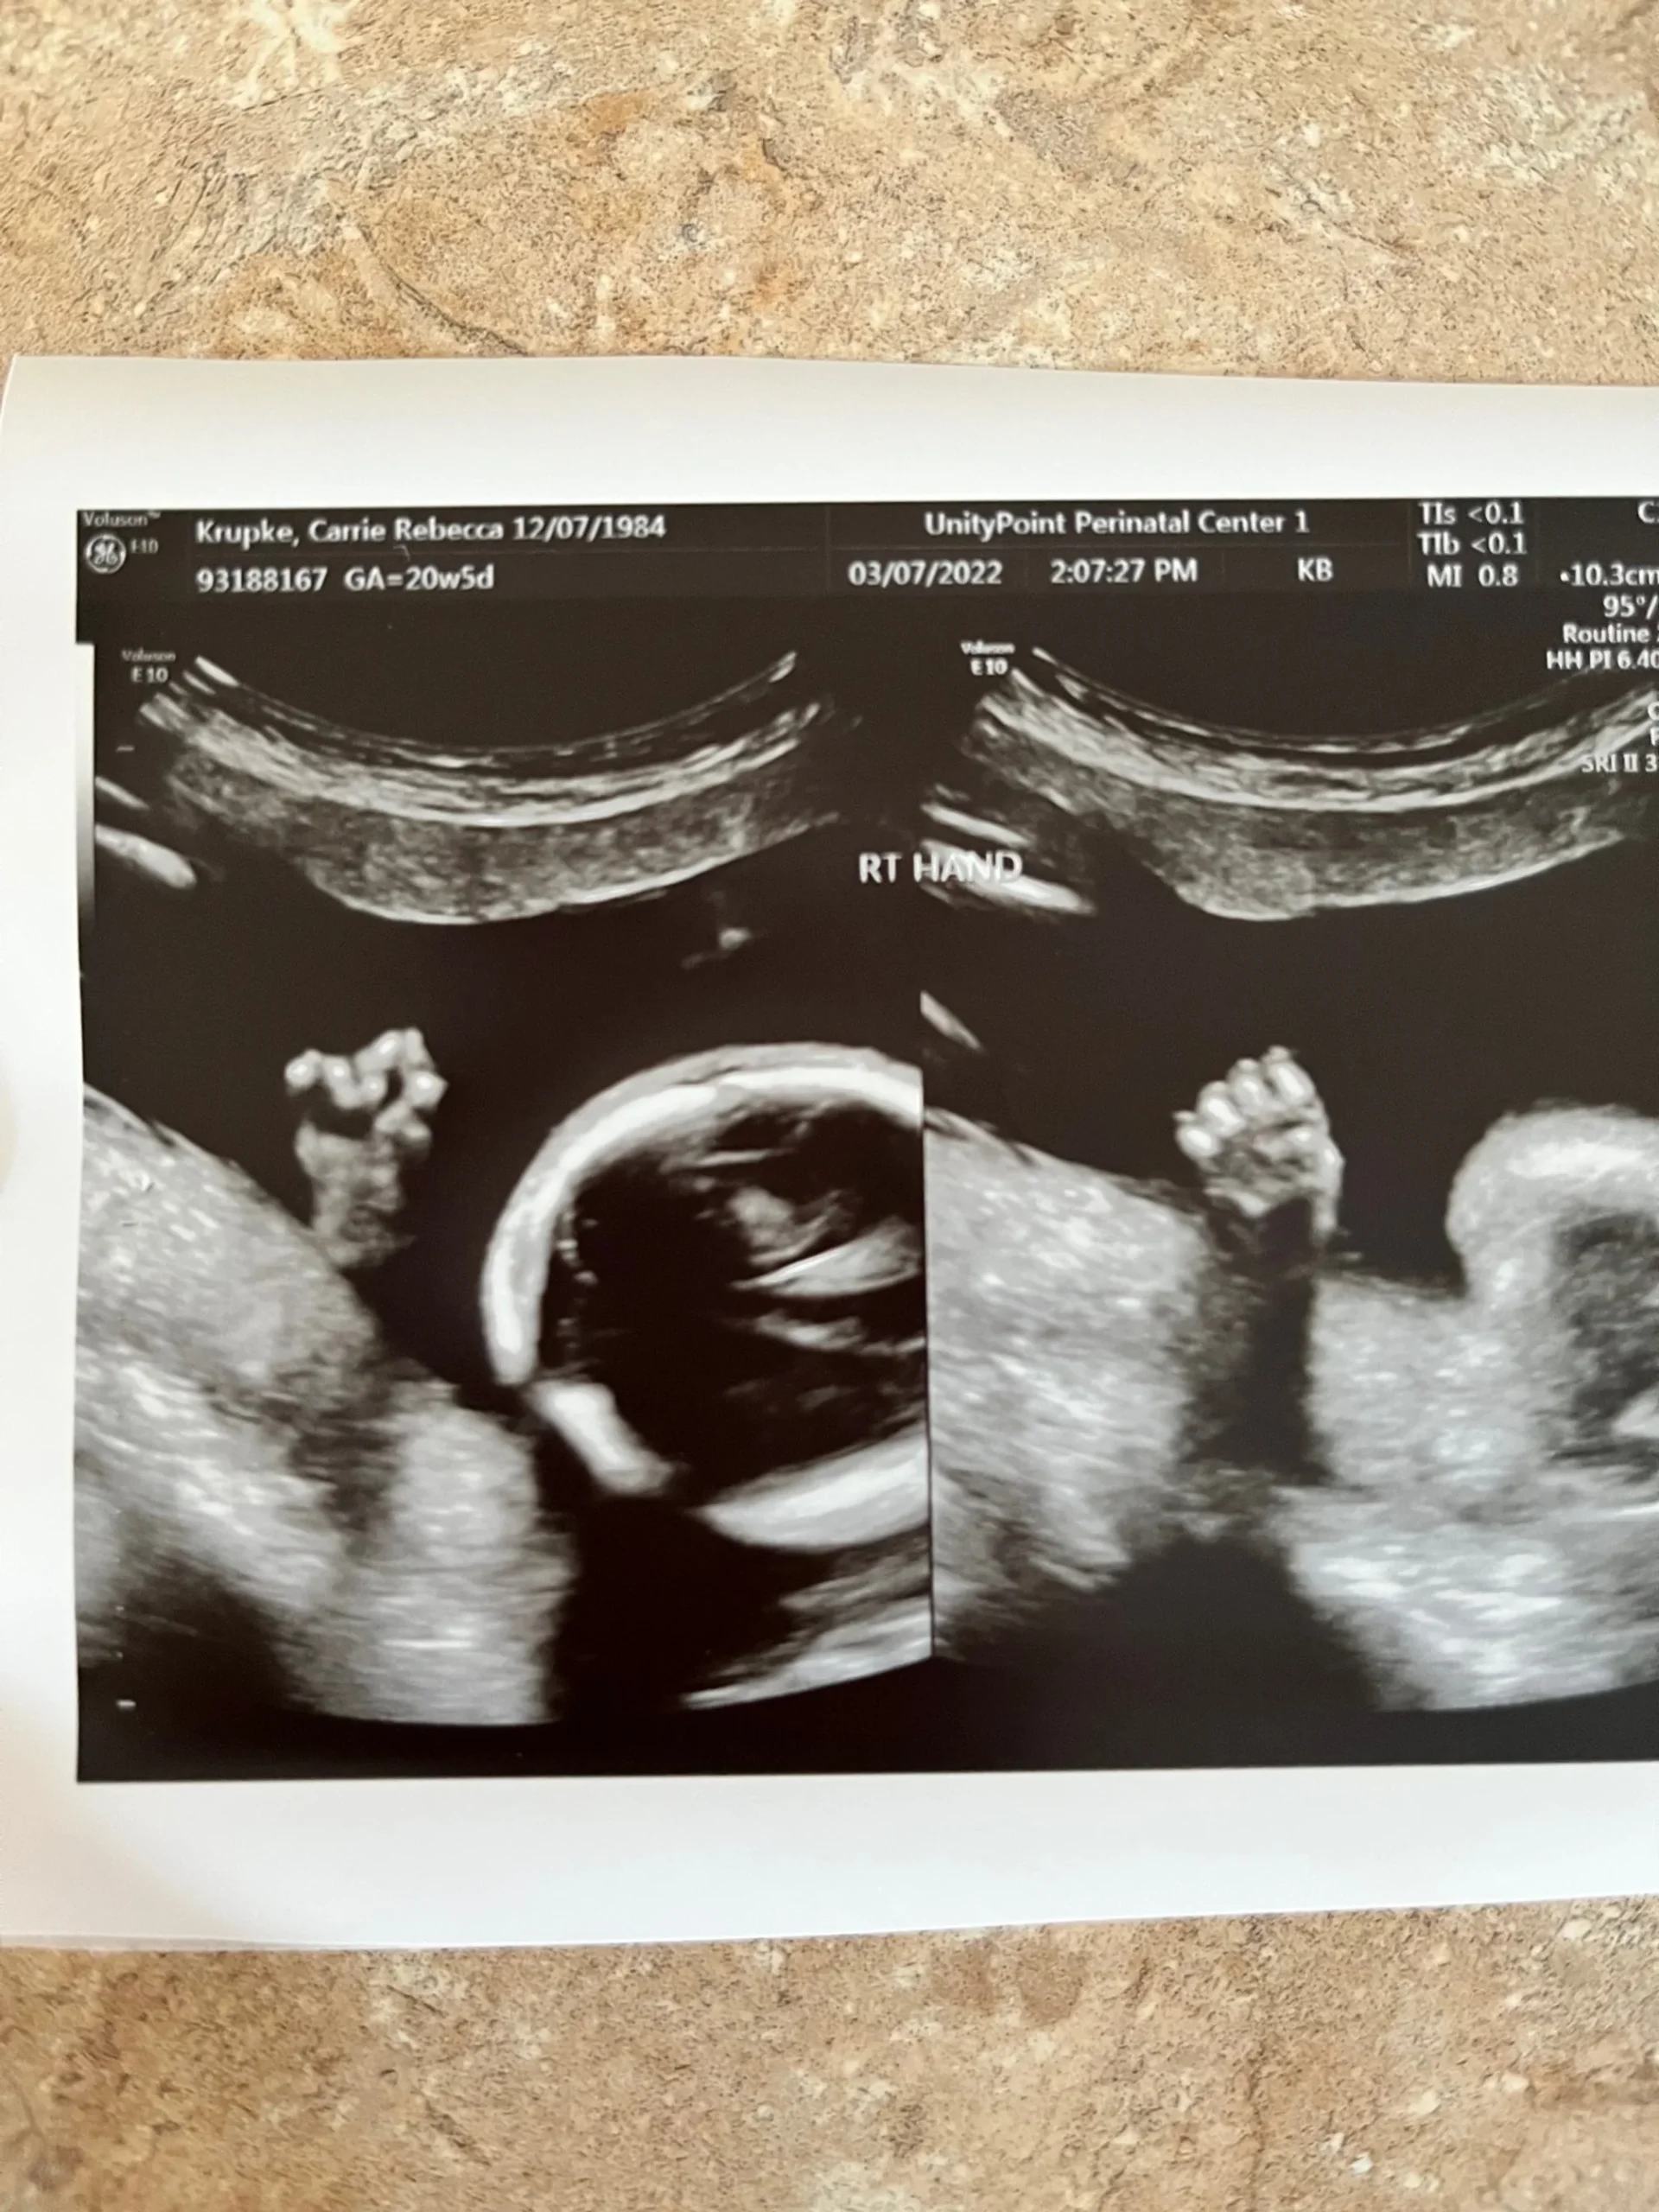

a punching right fist that clocked the ultrasound wand 🙂 She’s a fighter!